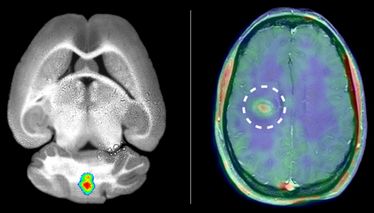

Die CiM-Forscher nutzten erstmals bestimmte Enzyme, die Matrix-Metalloproteinasen (MMPs), um die MS-typischen Entzündungen im Gehirn darzustellen. In einer Vorstudie hatten Biologen und Biochemiker um CiM-Sprecherin Prof. Lydia Sorokin festgestellt, dass diese Enzyme eine entscheidende Rolle spielen. Sie hatten Mäuse mit einer der Multiplen Sklerose ähnlichen Erkrankung untersucht und herausgefunden: MMPs ermöglichen Immunzellen, die Blut-Hirn-Schranke zu überwinden und ins Gehirn zu wandern, wo sie Entzündungen auslösen.

Um die Enzyme im Organismus zu markieren und in Bildern sichtbar zu machen, entwickelten Nuklearmediziner und Chemiker um CiM-Co-Koordinator Prof. Michael Schäfers einen "Spürstoff", im Fachjargon Tracer genannt. Diese chemische Substanz spürt die gesuchten Enzyme im Körper auf und bindet sich an sie. Die Chemiker koppelten einen Fluoreszenz-Farbstoff an den MMP-Tracer, dessen Lichtsignale sich mit optischen Verfahren messen lassen. Über das Tracersignal konnten die Forscher zunächst bei Mäusen auf die Aktivität der Enzyme schließen. "Wir stellten fest, dass die Beobachtung der MMPs präzise Informationen darüber liefert, wo Immunzellen die Blut-Hirn-Schranke durchwandern und wo Entzündungen im Gehirn vorkommen", sagt Molekularmedizinerin Dr. Hanna Gerwien.